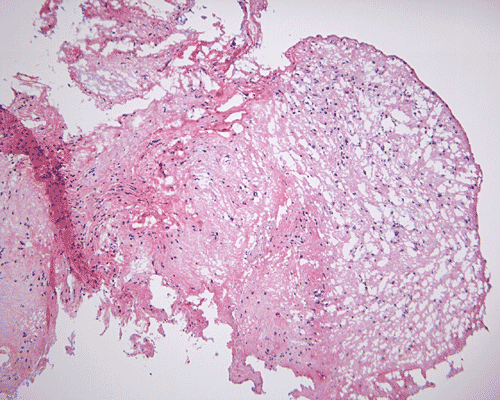

Pathology of the case: A small specimen was obtained by endoscopic biopsy. The specimen cannot be smear out after being squashed and remain as several, large, stellate-shaped cohesive clumps (Panel D). The edges of these clumps are relatively thin and allows better observations. The nuclei do not appear to be pleomorphic. Many elongated cytoplasmic processes can be seen (Panel E) and are suggest a glial nature of these cells. The lesion gives a spongy appearance on low-magnification (Panel F). On medium-magnification, there are some clustering of nuclei (Panel G). On high-magnification, the nuclei appear hyperchromatic and pointy but no substantial pleomorphism, prominent nucleoli, or mitotic figure. Some bluish, mucoid material is identified in some microcysts (Ú in Panel H).

There is no endothelial proliferation or necrosis. An  intraoperative diagnosis of glial neoplasm was made. The lesion was entirely resected. On paraffin section, the lesion has a hypocellular background decorated by many small microcysts, often in clusters, that contain mucoid material and small cluster of nuclei that resemble bundles of flowers (Panel I and J).  The nuclei are bland. There was no mitosis, endothelial proliferation or necrosis (Panel K and L).